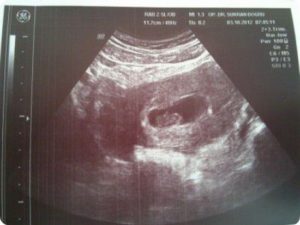

Узи 8 недель беременности

Узи 8 недель беременности: при беременности 8 недель уже можно различить ножки, ручки, просматривается позвоночник. Сердце занимает около 50% грудной клетки и бьется с частотой 160 уд/мин.